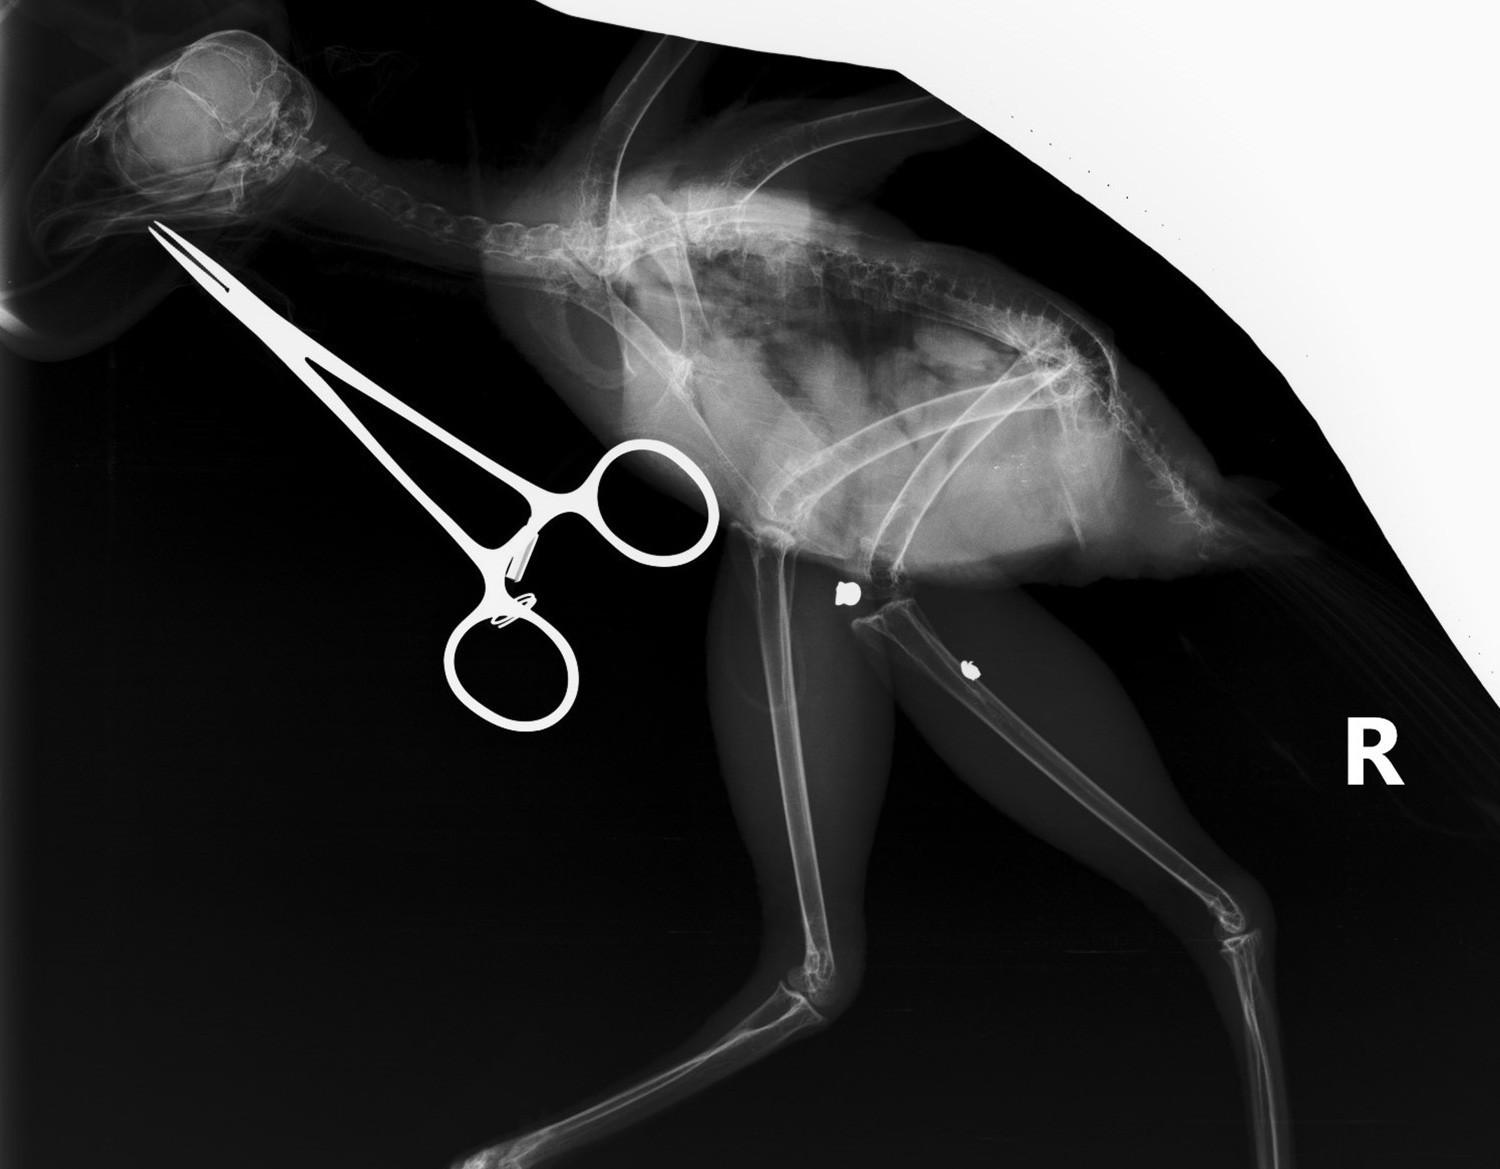

該隻鳳頭鷹最近因翅膀受傷,被送到園方的野生動物拯救中心。在進行X光檢查時,團隊發現牠的腿部隱藏著另一處傷勢,牠的右腿曾被氣槍鋼彈擊中。衝擊力不但打斷了右腓骨,還使鋼彈碎裂,一塊較大的碎片移動到去膝關節,另一塊較小的碎片則嵌入脛跗骨中。園方分析這個傷勢已經有一段時間,令人意外是該隻鳳頭鷹仍能正常使用牠的腳和爪。

園方通過一個小的皮膚切口,輕鬆取出較大的鋼彈碎片;至於較小且深的碎片,則因移除的風險大於好處,而被保留下來。經過幾天的傷口處理後,資深獸醫為鳳頭鷹受傷的翅膀進行了修復手術。鳳頭鷹目前康復進度良好,並正在進行康復訓練,為重返大自然做好準備。